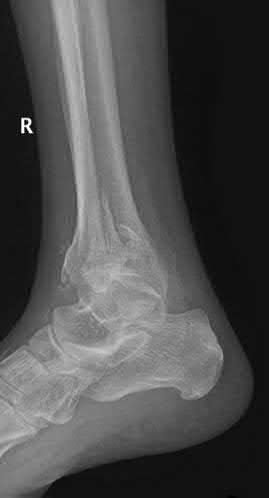

A 28-year-old male sustains a severe hyper-dorsiflexion injury to his ankle in a motor vehicle accident, resulting in a Hawkins Type III talar neck fracture. Which of the following arteries provides the predominant blood supply to the body of the talus, placing it at significant risk for avascular necrosis in this injury?

Options:

- Artery of the sinus tarsi

- Anterior tibial artery

- Dorsalis pedis

- Artery of the tarsal canal

- Peroneal artery

Correct Answer: Artery of the tarsal canal

Explanation:

The artery of the tarsal canal, which is a branch of the posterior tibial artery, provides the dominant blood supply to the talar body. In a Hawkins Type III fracture (talar neck fracture with subtalar and tibiotalar dislocation), the blood supply from the artery of the tarsal canal, the artery of the sinus tarsi, and capsular vessels are disrupted, leading to an avascular necrosis (AVN) rate approaching 100%.